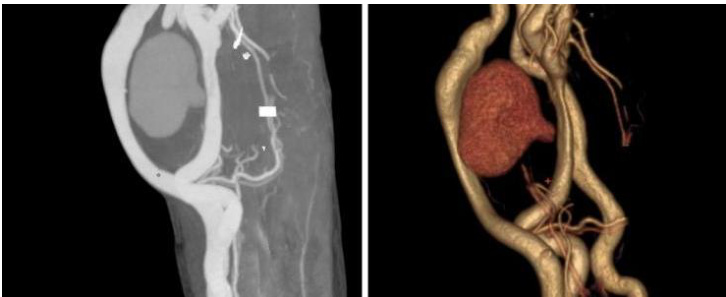

② 左上肢血管 CTA:左前臂动静脉内痿术后,前臂软组织肿胀,肱动脉与贵要静脉间可见类圆形团块影,其内可见片状高密度影及周围环绕低密度影,大小约 4.7cm× 4.4cm,肱动脉似见小破口。

图 2. 上肢血管 CTA 及重建,明显可见肱动脉破口及造影剂流经假性动脉瘤腔内形成的椭圆形瘤腔。